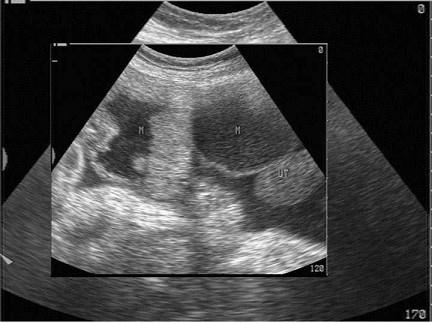

问题 女性,46岁,发现腹部肿块1个月余。妇科检查:盆腔触及包块。超声检查如图,最可能的诊断为?(?)

选项 A.囊腺癌 B.囊腺瘤 C.黄体囊肿 D.转移性卵巢癌 E.包裹性积液

答案 B